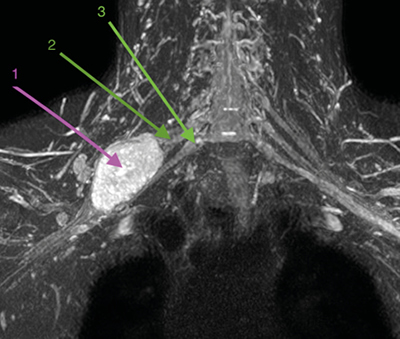

Con la orientación diagnóstica inicial de schwannoma de plexo braquial derecho con escasa repercusión clínica, se decidió actitud expectante. Se instauró tratamiento analgésico de primer escalón y ansiólisis a demanda para dormir. El paciente era reticente al tratamiento neuromodulador debido a sus efectos secundarios. Seis meses después, tras una nueva RM de control, se observó un discreto crecimiento de la lesión con probable efecto compresivo por los músculos escalenos anterior y medio (Figuras 1 y 2). Se indicó una infiltración diagnóstico-terapéutica con toxina botulínica tipo A (Botox®) ecodirigida. Las crisis de dolor eran más frecuentes y de más minutos de duración y empezaban a afectar su calidad de vida. EVA 2-3 en reposo, 8-9/10 en las crisis.

Fig. 1. RM coronal en T1. 1. Schwannoma de plexo braquial derecho. 2. Músculo escaleno anterior izquierdo, para mostrar su ubicación relativa al plexo braquial ipsilateral, dado que en el lado derecho no se identifica claramente. 3. Músculo escaleno medio derecho